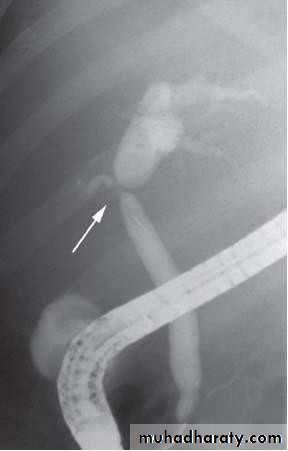

• MRCP

• Magnetic resonance cholangio- pancreatography crosssectional

• image demonstrating a hilar mass (thick• arrow) and gallstones (thin arrow)